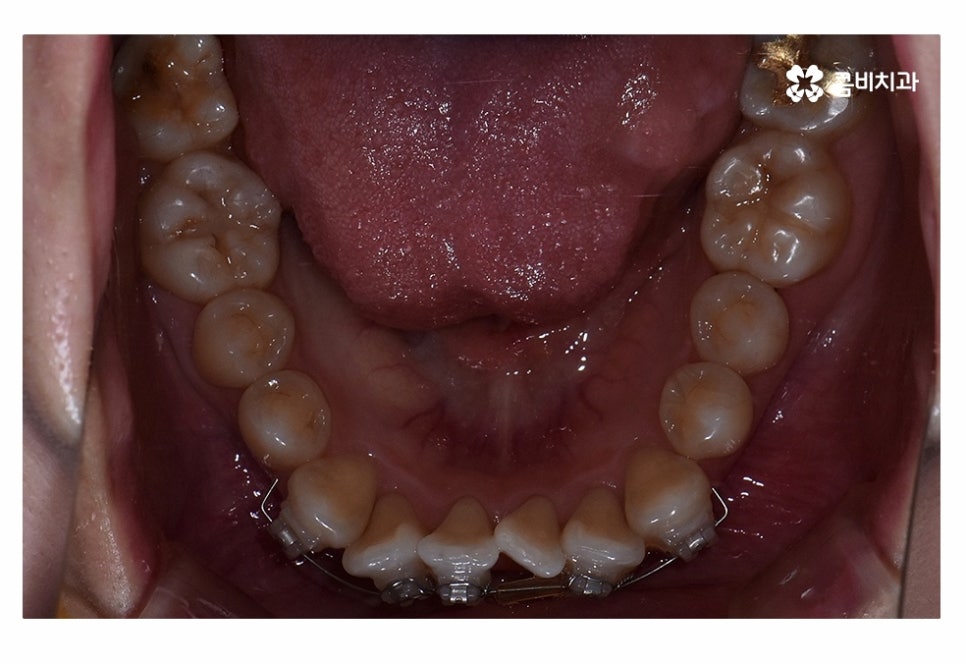

오늘은 치아부분교정 사례와 함께 부분교정에 대한 설명을

해드릴 예정이며 위 사진에서 보시는 환자분의 경우

정면에서 보는 치열과 측면의 차이가 다소 크다는 것을 알 수 있는데요.

이처럼 치열은 정면에서 보이는 것만이 아닌 얼굴형과 골격을

고려하여 치료 계획을 세워야 한다는 것을 알 수 있어요.

교합이 정상적이고 치아의 이동 공간을 고려할 때

치아부분교정이 가능했던 환자분이었기 때문에 윗니와 아랫니에

각각 부분교정이 진행된 사례라고 할 수 있는데요.